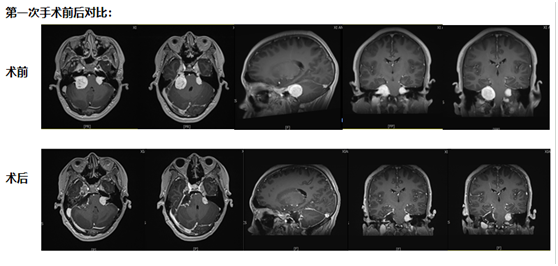

第一次手術:從耳后開口,既要拆瘤又要保聽力

考慮到小倪才21歲,團隊沒選 “一刀切” 的方案,而是決定從耳后開一個約10厘米的小口 ——這個位置能精準摸到耳朵旁邊的腫瘤,還能盡量避開控制聽力、面部活動的神經。

手術當天,醫生在顯微鏡下一點點 “剝” 腫瘤:剝到腫瘤深處時,醫生發現再往里切,必然會傷著聽力神經。“停!這里留一點點,先保聽力。”團隊果斷調整,把能安全切除的腫瘤全清干凈,再仔細止血,避免術后出血。